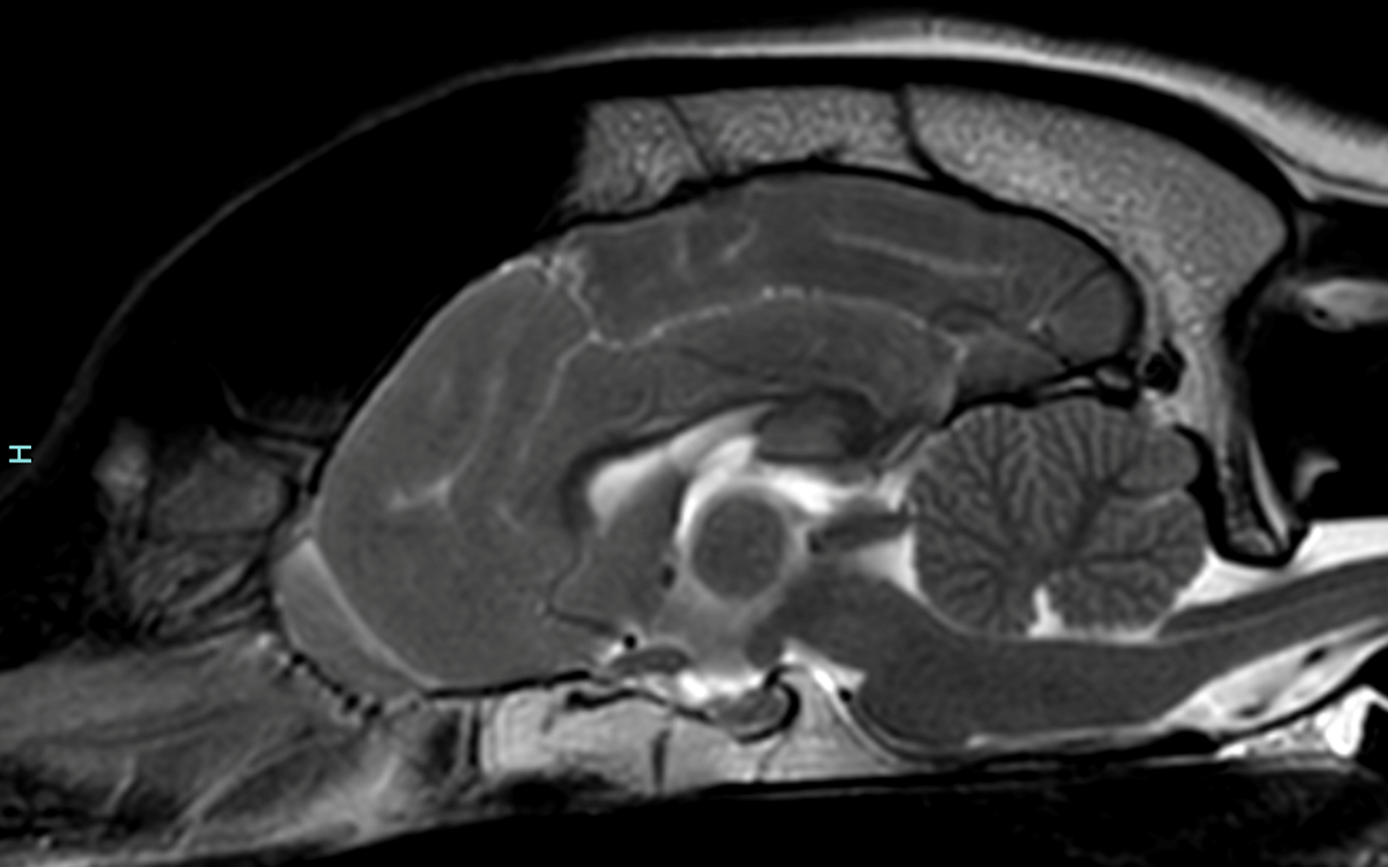

Dogs need to be referred by their vet for VNS assessment. We can implant these devices in any dog that can tolerate wearing a collar and has been diagnosed with epilepsy following appropriate confirmation of seizures, blood samples and an MRI (Magnetic Resonance Imaging) scan of the brain.